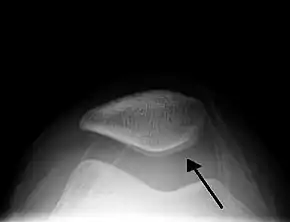

Skyline view of the patella demonstrating a large joint effusion as marked by the arrow